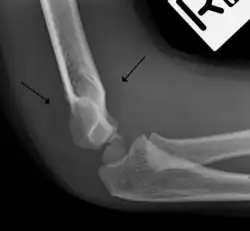

Anterior sail signs as well as posterior fat pad in a child with a supracondylar fracture.